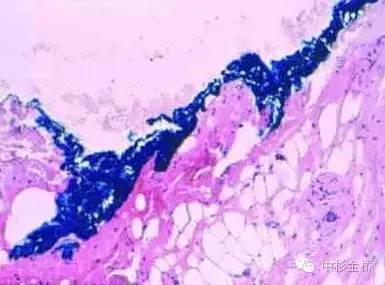

3、應(yīng)用于脂肪組織時,可用噴壺噴灑少量丙酮對組織表面進(jìn)行脫脂處理,擦拭干后再使用色標(biāo)劑進(jìn)行染色。尤其適用于乳腺和皮下組織。

5、染色后組織可用福爾馬林固定或冷凍切片。